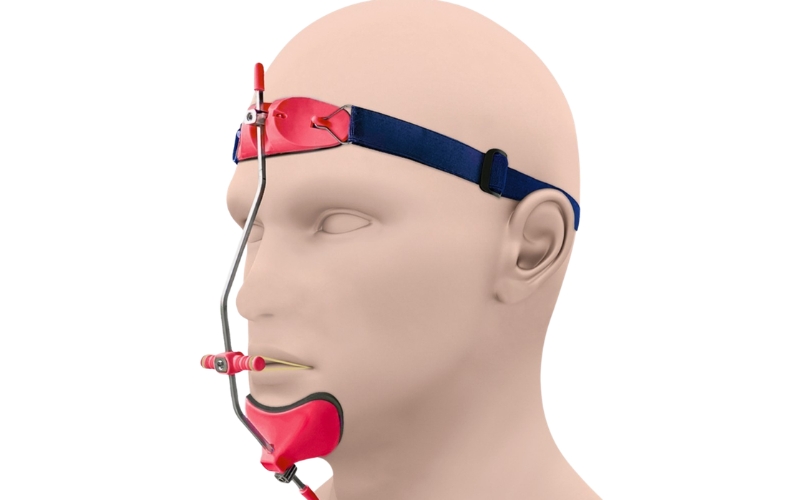

الأجهزة التقويمية خارج الفموية

- قد يُستخدم جهاز الفيس ماسك لتحفيز التقدم الأمامي للفك العلوي في الحالات المناسبة

- وقد يُستخدم الهيدغير للمساعدة في الحد من النمو الأمامي للفك العلوي أو دعم تصحيح بعض علاقات الإطباق

- يساعد في توجيه نمو الوجه خلال التطور

- مفيد في بعض حالات سوء الإطباق الهيكلي المختارة

- قد يخفف من شدة بعض المشكلات التقويمية المستقبلية

- يكون أكثر فعالية عند استخدامه في المرحلة المناسبة من النمو